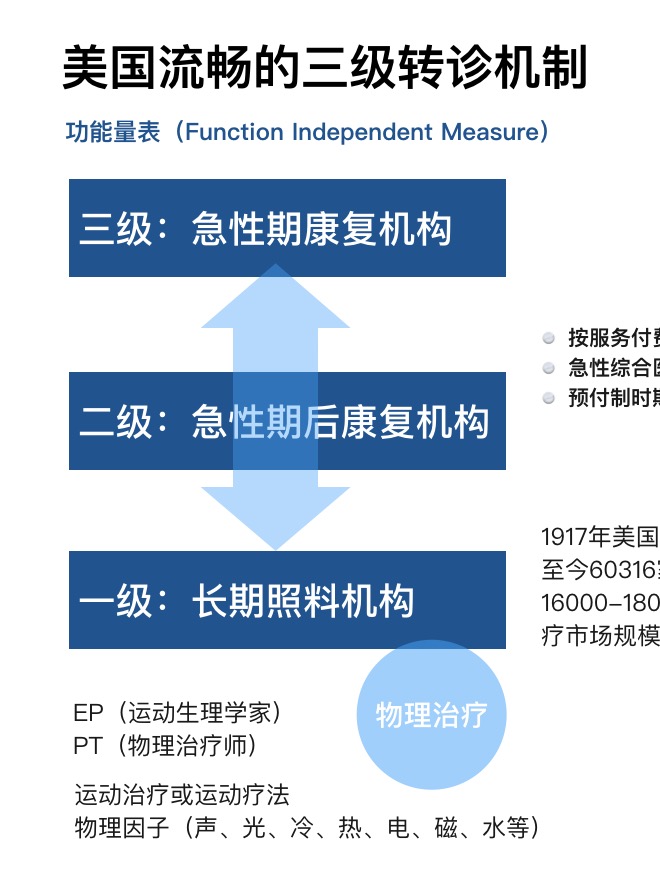

- 从DRGs到FRGs,看美国康复医疗机构发展情况 BuGu ,2020-05-05

- 我们前面给大家详细介绍了康复产业:康复医疗:政策、需求双轮驱动下的产业爆发 那么康复医疗在其他发达国家/地区的发展情况如何,他们已形成的成熟的康复市场是否对我国康复行业的发展有一定的借鉴意义? 我们将以美国康复医疗体系为例,分别从发展历程、现状和康复人才的培养机制三方面,为大家介绍成熟康复医疗行.....

- 美国早期物理医学和康复的历史 BuGu ,2020-04-27

- 在20世纪80年代和之后的几十年里,住院病人康复项目(由医疗保险和医疗补助服务中心(CMS,前身是卫生保健融资管理局(HCFA))所称的住院病人康复设施)在美国各地扩展。医疗照顾住院病人康复设施前瞻性付款系统(PPS)于2001年生效。在接下来的二十年里,住院病人康复的补偿也发生了进一步的变化。世界.....